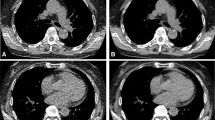

In CT, ionizing radiation exposure from the scan has attracted much concern from patients and doctors. This work is aimed at improving head CT images from low-dose scans by using a fast Dictionary learning (DL) based post-processing. Both Low-dose CT (LDCT) and Standard-dose CT (SDCT) nonenhanced head images were acquired in head examination from a multi-detector row Siemens Somatom Sensation 16 CT scanner. One hundred patients were involved in the experiments. Two groups of LDCT images were acquired with 50 % (LDCT50 %) and 25 % (LDCT25 %) tube current setting in SDCT. To give quantitative evaluation, Signal to noise ratio (SNR) and Contrast to noise ratio (CNR) were computed from the Hounsfield unit (HU) measurements of GM, WM and CSF tissues. A blinded qualitative analysis was also performed to assess the processed LDCT datasets. Fifty and seventy five percent dose reductions are obtained for the two LDCT groups (LDCT50 %, 1.15 ± 0.1 mSv; LDCT25 %, 0.58 ± 0.1 mSv; SDCT, 2.32 ± 0.1 mSv; P < 0.001). Significant SNR increase over the original LDCT images is observed in the processed LDCT images for all the GM, WM and CSF tissues. Significant GM–WM CNR enhancement is noted in the DL processed LDCT images. Higher SNR and CNR than the reference SDCT images can even be achieved in the processed LDCT50 % and LDCT25 % images. Blinded qualitative review validates the perceptual improvements brought by the proposed approach. Compared to the original LDCT images, the application of DL processing in head CT is associated with a significant improvement of image quality.